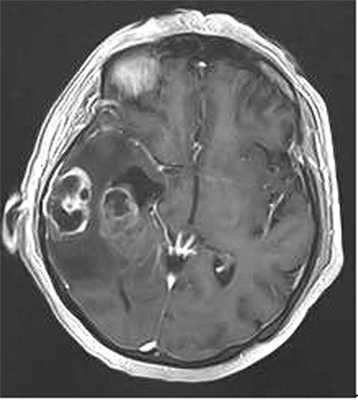

Наблюдение 1. У пациентки 70 лет за 2 мес до госпитализации появилась и стала нарастать слабость в левых конечностях, ухудшилась память на текущие события, снизилась критика собственного состояния. При магнитно-резонансной томографии (МРТ) была диагностирована внутримозговая опухоль правой височной доли с зоной перифокального отека (рис. 1).

Рис. 1. Наблюдение 1. МРТ перед операцией. Внутримозговая опухоль правой височной доли с зоной перифокального отека.